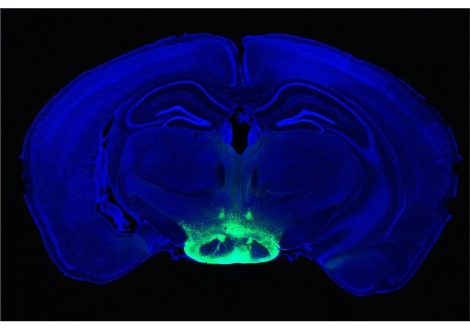

لا تكون مثبطات المناعة القياسية المستخدمة في عمليات زرع الأعضاء من إنسان إلى آخر فعالة إذا كان الجهاز المناعي يصنع الكثير من الأجسام المضادة ضد العضو المزروع ، كما يخشى الجراحون أن يكون هذا هو الحال مع قلب الخنزير . يوقف KPL-404 إنتاج هذه الأجسام المضادة عن طريق الارتباط بمستقبل خلوي يسمى CD40 ، مما يثبط نشاط الخلايا البائية المنتجة للأجسام المضادة ، ويثبط عملها المتبادل مع الخلايا التائية التي تنسق استجابة الجهاز المناعي للغزاة . يقول محي الدين: "الجينات العشرة المعدلة تساعد ، لكن الجسم المضاد لـ CD40 ، الذي كان محور تركيزي الرئيسي طوال مسيرتي المهنية ، أعتقد أنه سيغير قواعد اللعبة".